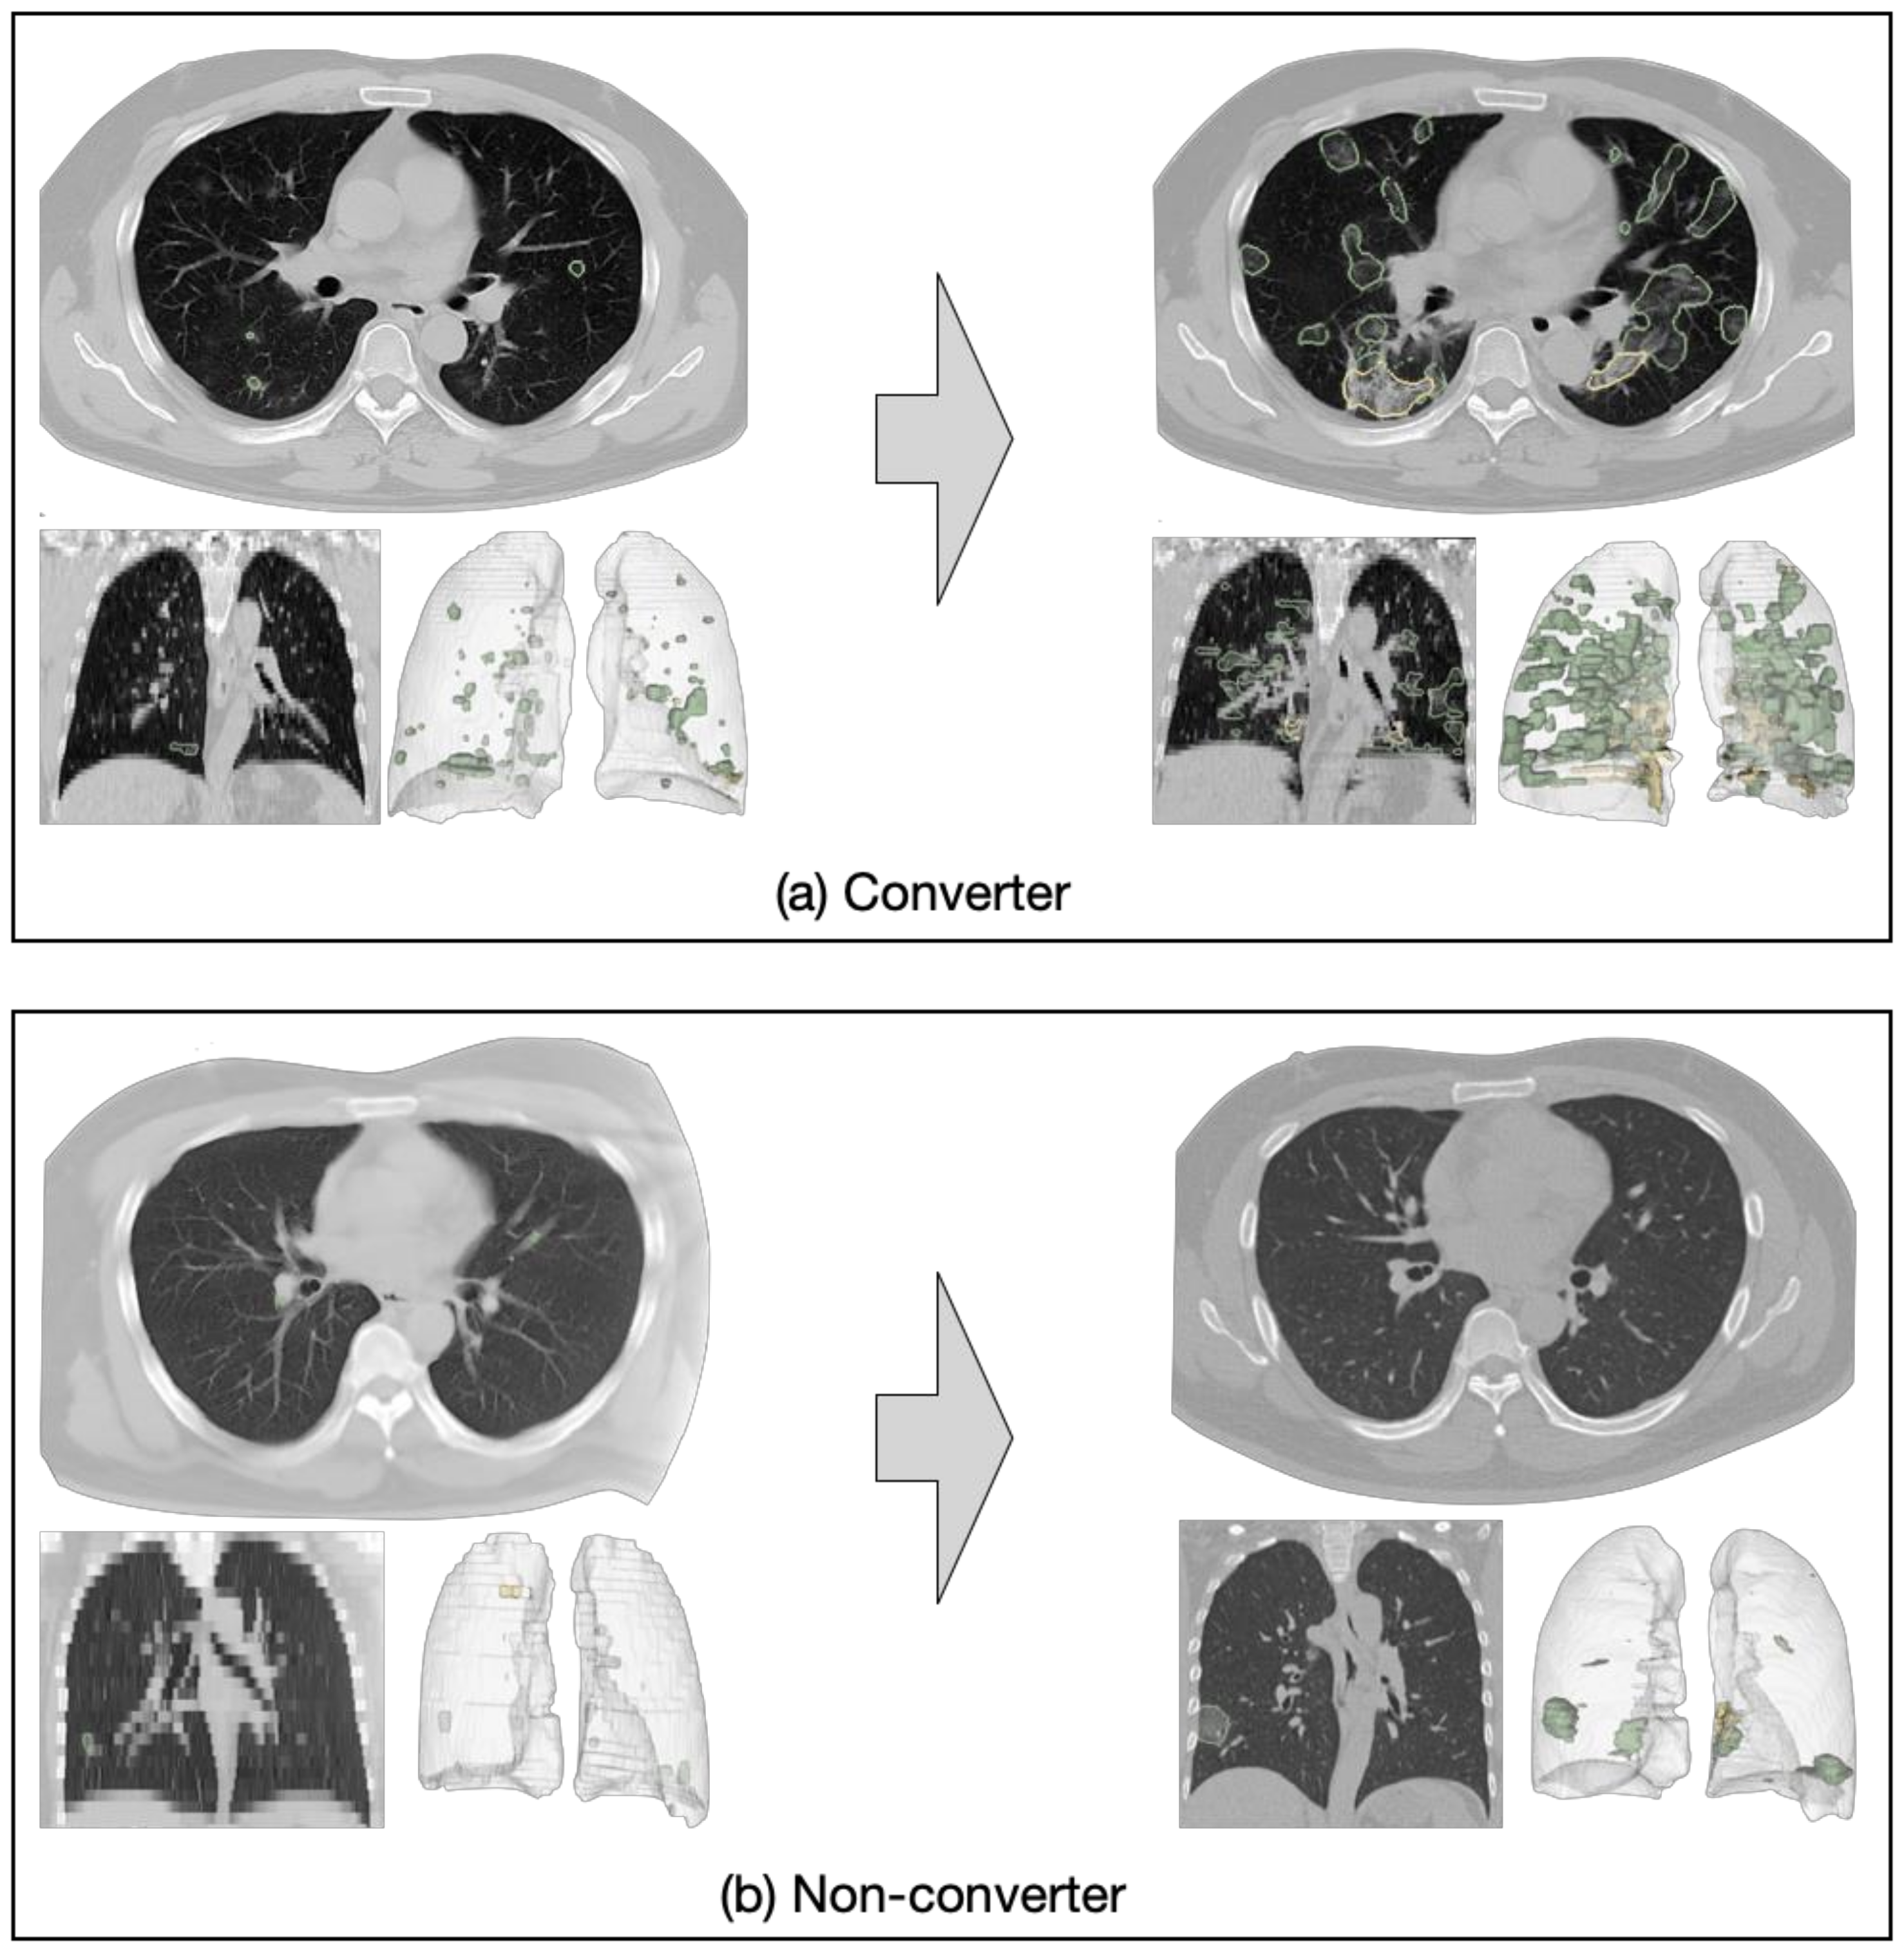

4.3. Progression Prediction